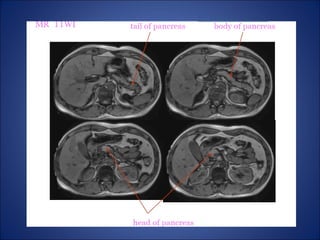

• On T1 WI:

– Has the highest T1 signal of all

abdominal organs and used for:-

1. precontrast T1- weighted images are

the most sensitive sequence to

detect focal lesions, which are often

hypointense relative to normal

parenchyma

2. for detection of hemorrhage within

inflammatory collections.

• On T2 WI:

– Slightly hyperintense compared to the

adjacent muscle, and used for

depicting the ductal anatomy, cystic

lesions, and islet cell tumors, which

are hyperintense compared to normal

pancreas.